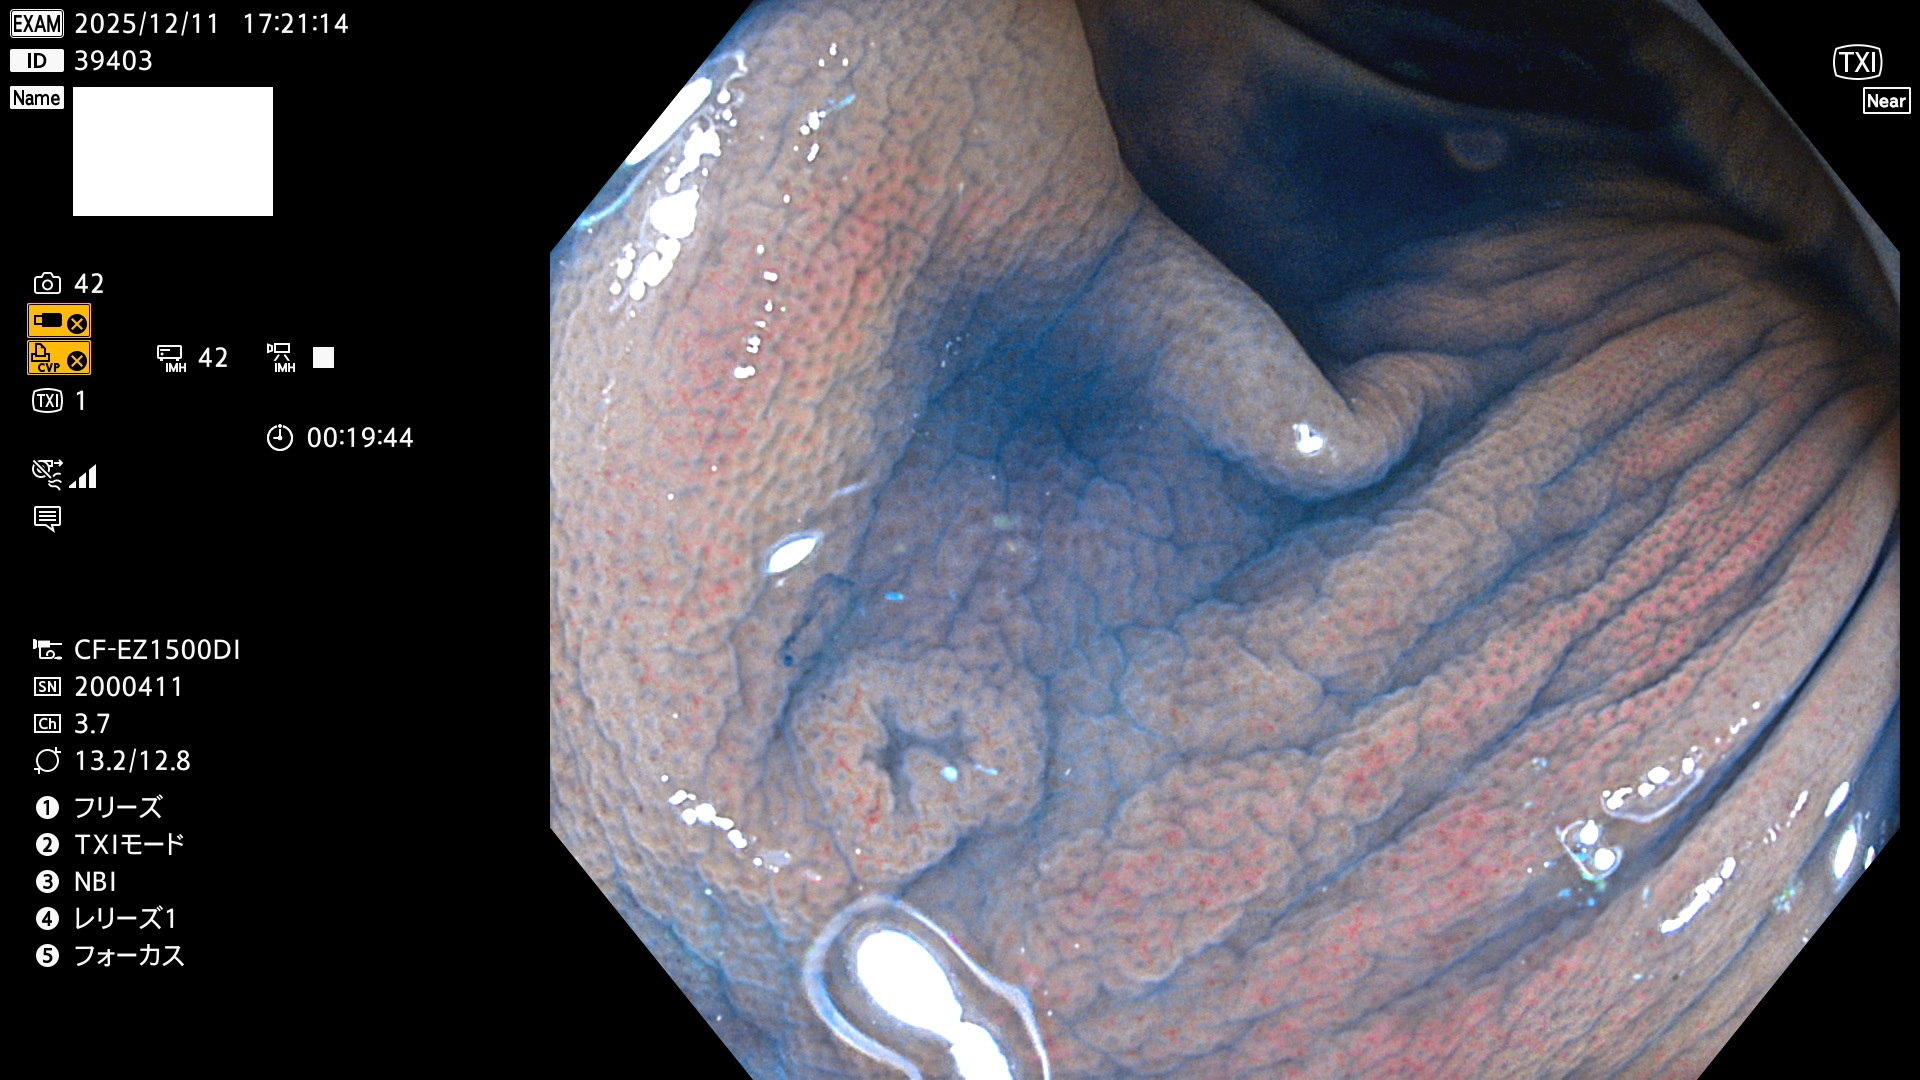

完全に平坦な物をUb、陥凹している物をUcと呼びます。Ubは認識が困難で、Ucはびらん(炎症)と紛らわしいために見落とされやすく、「内視鏡後・大腸癌」の原因になります。

専門的)Uc=De Novo癌? 内視鏡の解像度が低かった時代、このような説もありました。しかし今日の高精度内視鏡では良性の微小なUc型腺腫(APC遺伝子異常の腺腫)が日常的に見つかります。Ucこそが多段階発癌(Adenoma-Carcinoma Sequence)のMain Routeです。

毎週の検査(木・金・土・日)に発見されたUbとUc型・腺腫を、その週の日曜の夜にUPし1週間、提示します。

2025年12月11日〜12月15日の4日間(50件)で6個 (Uc_ADR=6個/50人=12%)